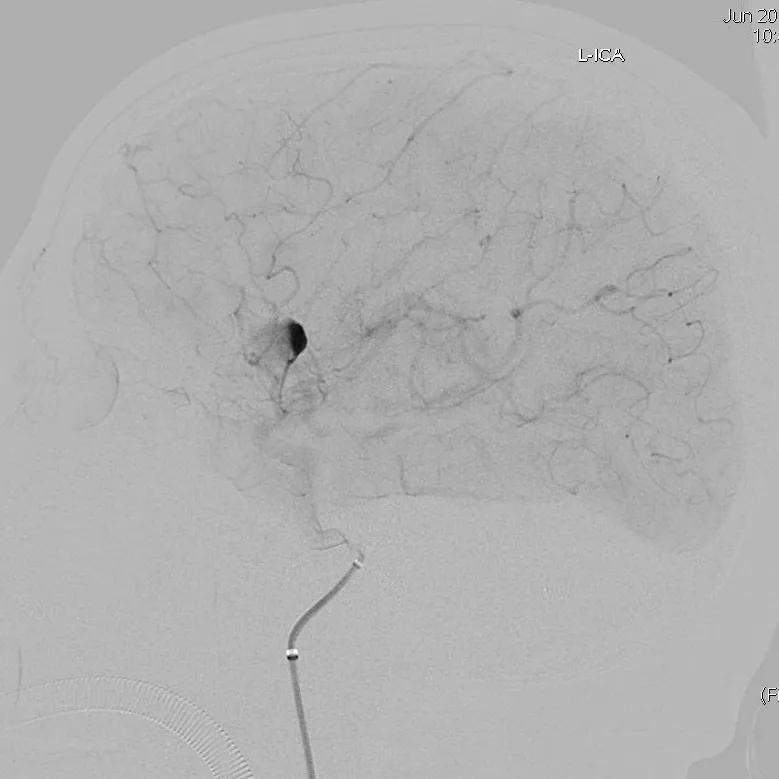

患者于入院前1天无明显诱因突发头。外院头颅CTA示:颅内动脉瘤。我院行DSA示:左侧大脑中动脉动脉瘤。

手术过程:

全脑血管造影可见左侧大脑中动脉动脉瘤,瘤体最大径:16.7mm,瘤颈宽:8.3mm。